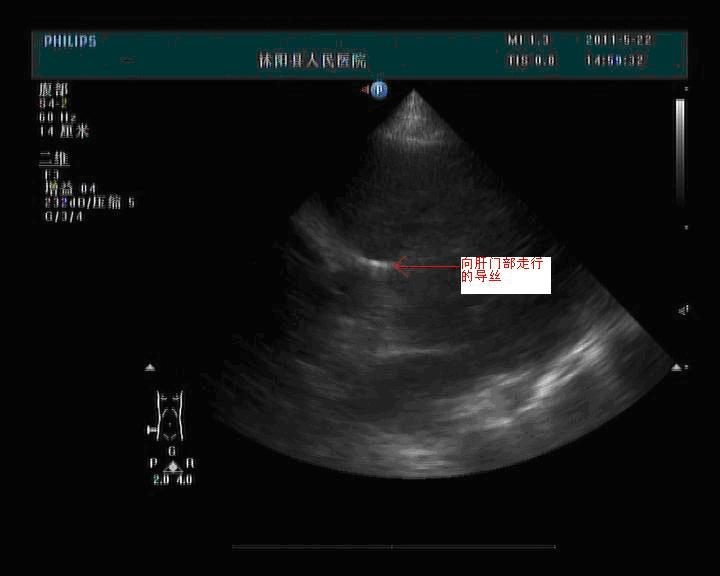

图2、超声清楚的看到导丝沿左肝内胆管向肝门部胆管走行。